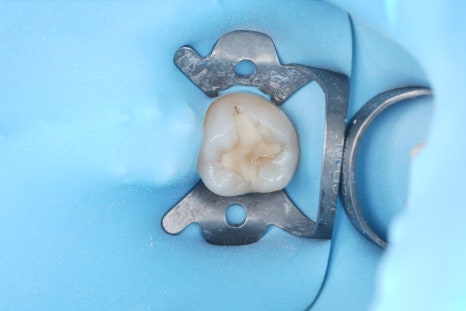

러버댐을 장착하고 수분이 닿지 않도록 격리한 다음, 한 층씩 빛으로 굳히면서 양옆 치아와 자연스럽게 어울리도록 형태를 잡아줘야 해요.

촬영일 : 250909